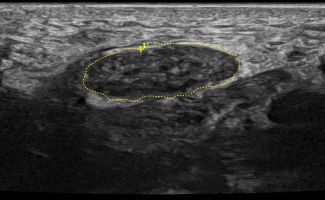

- Focal Lesions (tumors, neuromas)